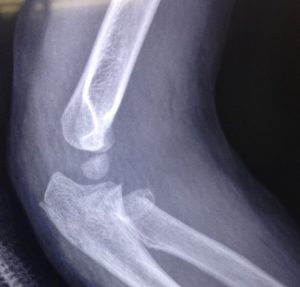

El tratamiento de las fracturas pediátricas ha evolucionado en las últimas décadas, y muchas lesiones que antes se manejaban de manera no quirúrgica ahora se están tratando quirúrgicamente. La Academia Estadounidense de Cirujanos Ortopédicos ha desarrollado pautas clínicas para ayudar a guiar la toma de decisiones y agilizar la atención al paciente para ciertas lesiones, pero muchos temas siguen siendo controvertidos *2, es importante que acudas con un experto, te dará la mejor opinión sobre los problemas del sistema músculo-esquelético de tu pequeño!!!